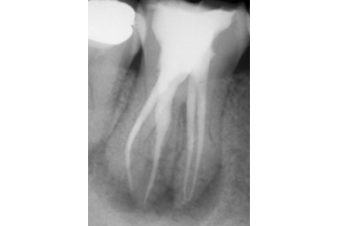

Three-dimensional imaging using CBCT is also very useful in identifying an additional root and treatment planning. It provides a ‘roadmap’ for endodontic treatment and highlights any curvatures present (Figure 5).

In a radix entomolaris, the main distal root (DB) may still have two canals (DB1 & DB2) (Figure 5). The DB2 is more difficult to locate and can be hidden in the isthmus between DB1 and DL. It is often in close proximity to DB1.

Use fine ultrasonics to conservatively open the isthmus to search for this canal (Figure 7).